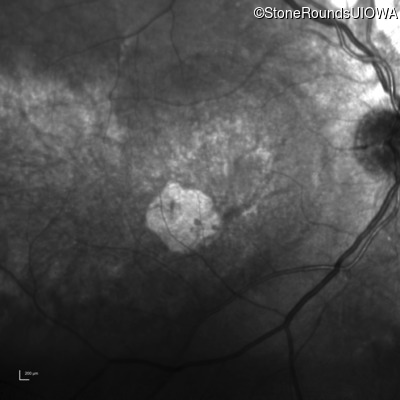

Infrared Fundus Photograph - Right - 20/80

Exemplar

Infrared Fundus Photograph - Left - 20/125